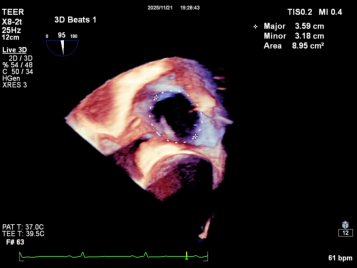

Annuloplasty Outcome:

Summary

The K-Clip® transcatheter tricuspid valve annuloplasty adopts a unique physiological annuloplasty technology with no damage to native valve leaflets. Even in the face of complex anatomical structures such as myxomatous degeneration of tricuspid valve leaflets, mild prolapse of the valve body and mild balloon-like changes, this technology can still accurately reduce the annulus and complete annulus remodeling.